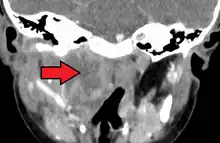

Large retropharyngeal abscess as seen on CT -

Large retropharyngeal abscess as seen on CT